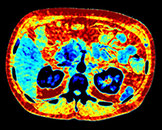

Выполните просмотр требуемой области с помощью нескольких решений благодаря эксклюзивному приложению Spectral Magic Glass для вычленения данных о составе тканей.

Здесь представлена серия изображений, на которых значения воксела обозначают эффективное атомное число. Эффективное атомное число может быть дробным, обозначающим какой-либо элемент, соединение или смесь. Данное число может отличаться от порядкового номера, указанного в периодической таблице. Единица для обозначения — Z.